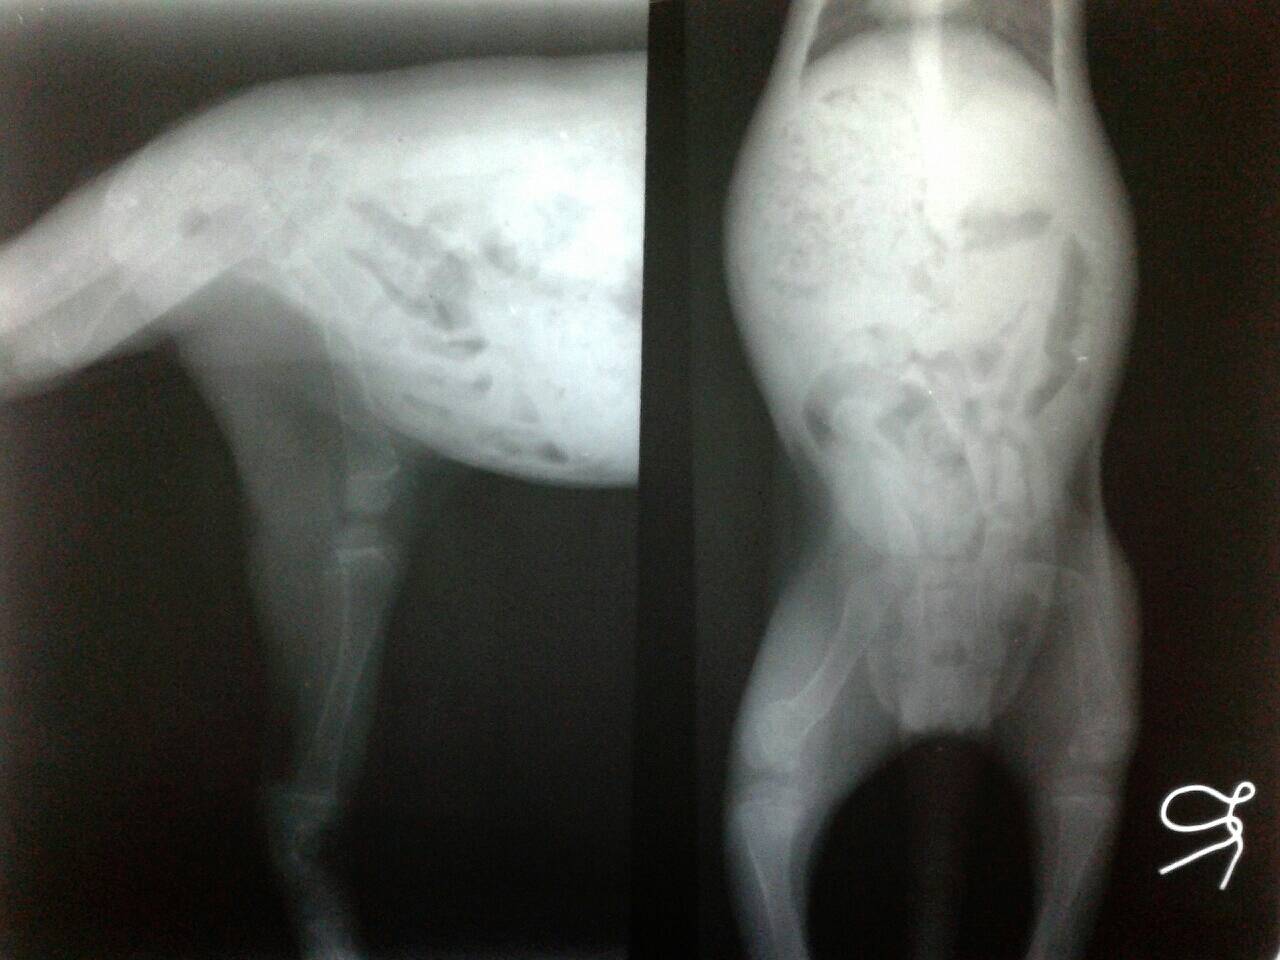

น้องเดินไม่ได้สงสารน้องค่ะ นอนร้องครางตลอดเลย น้องเเมวอายุ 2 เดือนกว่าๆเองเล่นซนจนกระดูกขาที่ติดกับกระดูกเชิงกรานหัก

วันนี้พาไปหาหมอที่คลีนิค "รักษ์สัตว์ ซอยลาซาล" คุณหมอบอกว่าเป็นเคสยากเพราะยังเด็ก ทางคลีนิคไม่มีเครื่องมือเพียงพอ

ให้ไปหาคุณหมอที่รพส.จุฬาหรือเกษตร เท่าที่หาข้อมูลเรื่องค่ารักษาอาการนี้ค่าใช้ค่อนข้างสูง